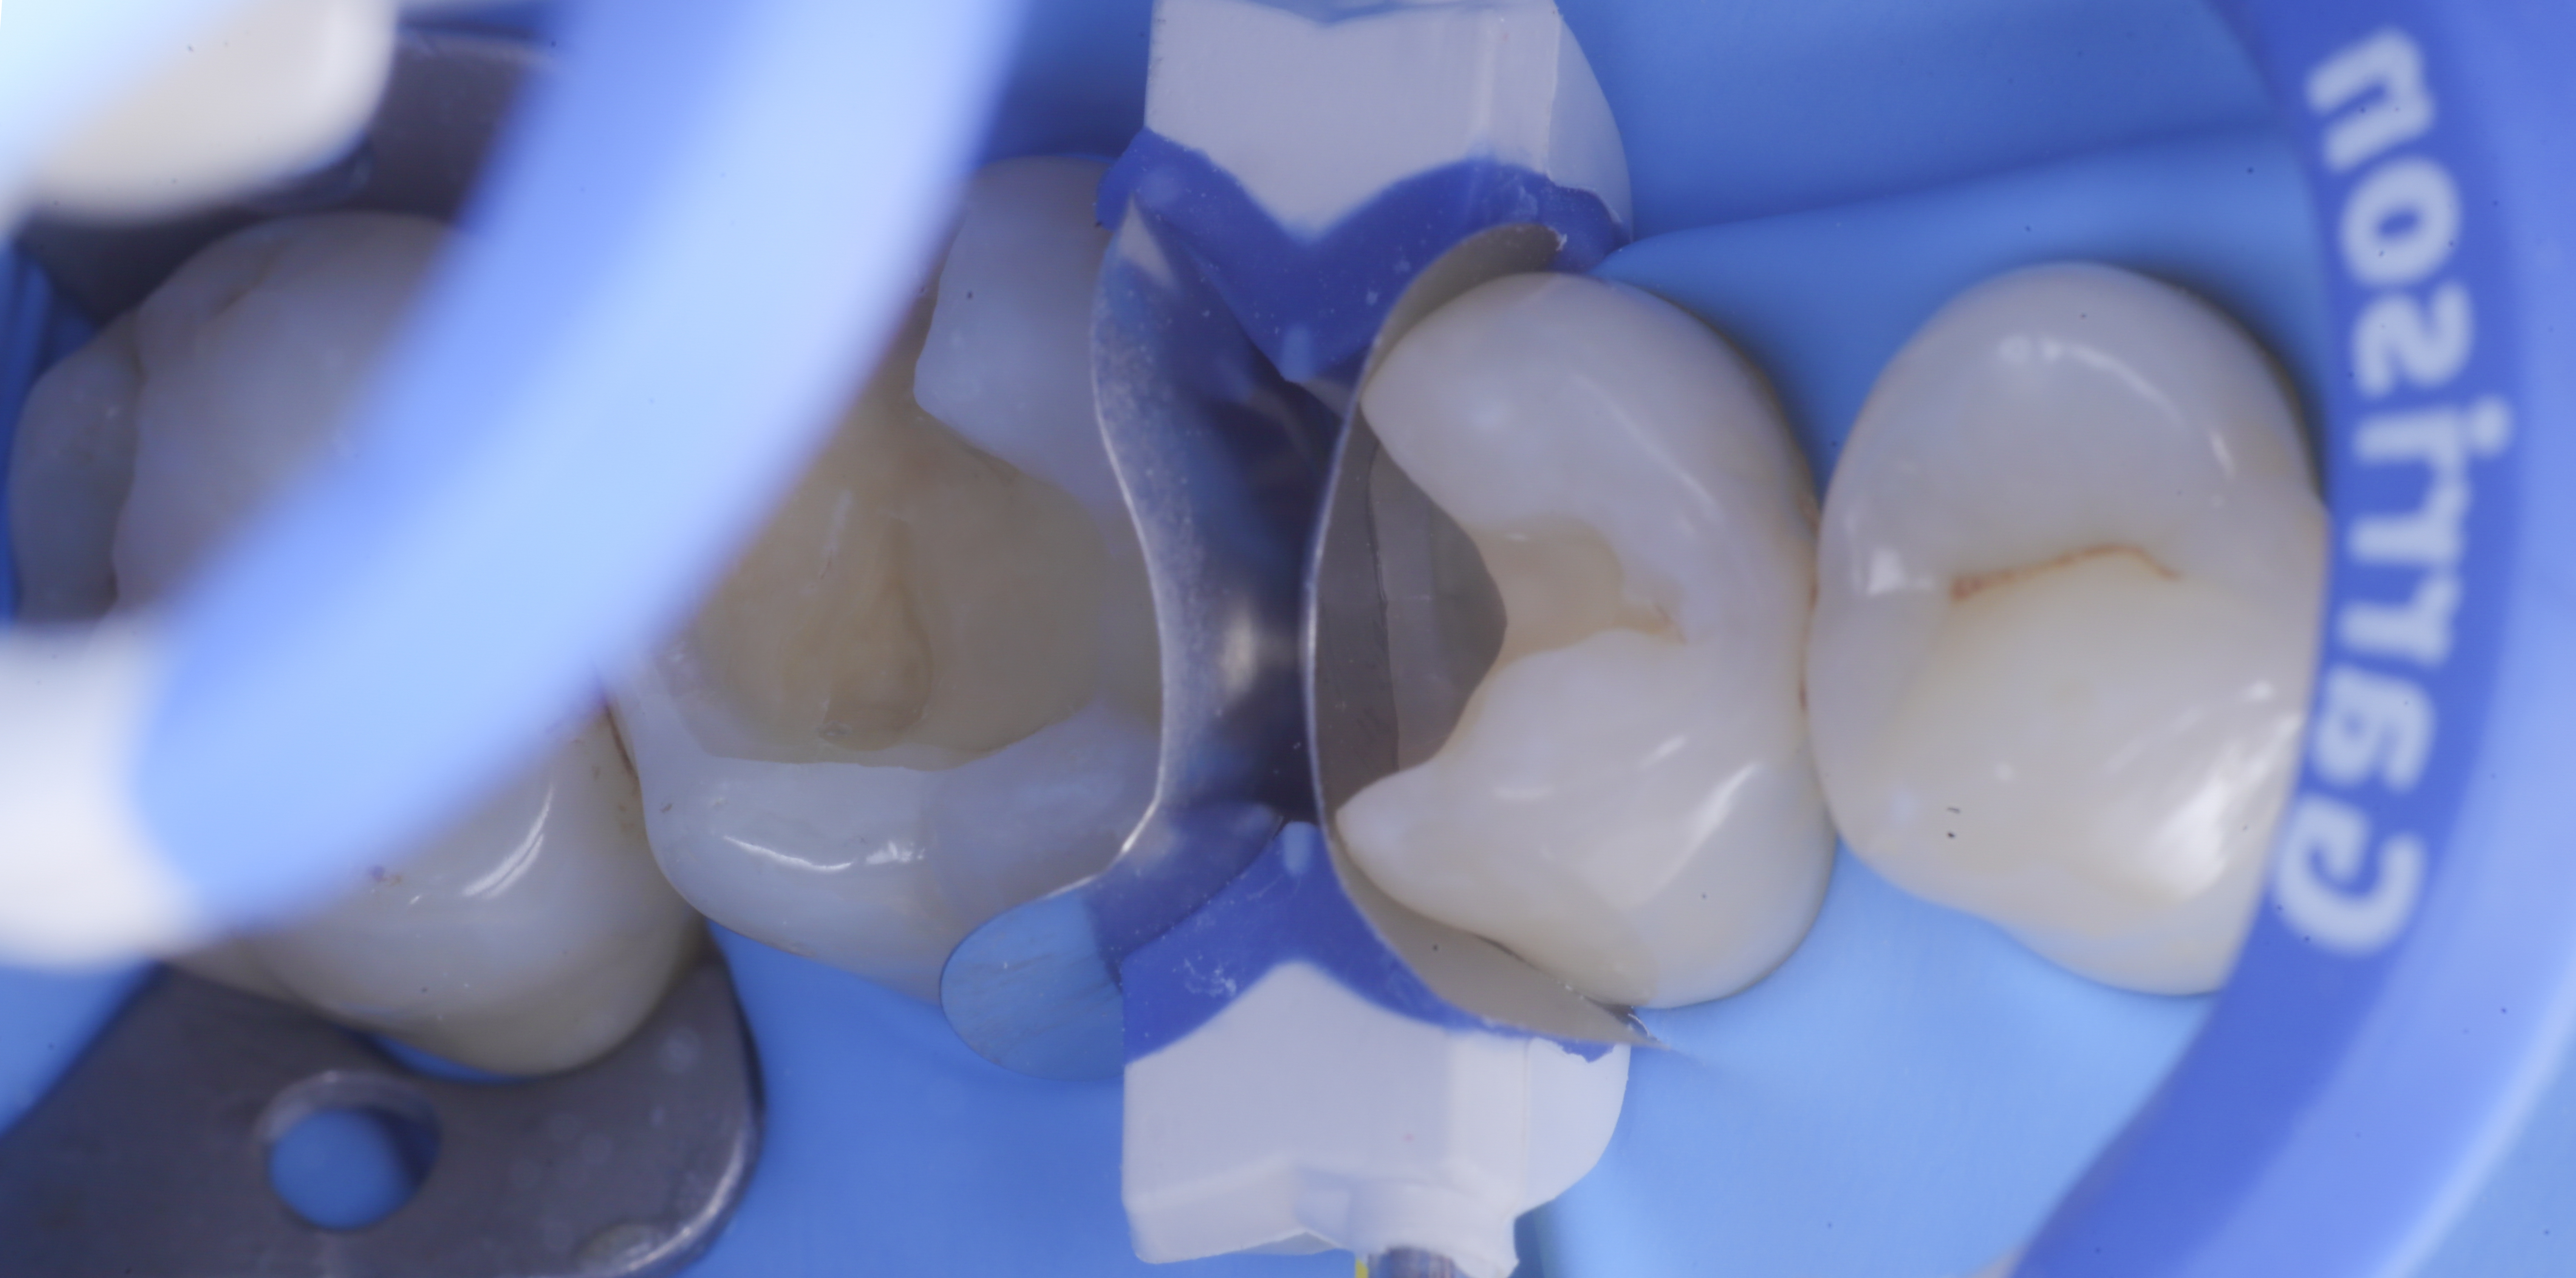

foto 2 Isolamento e aspetto delle cavità ultimate

foto 3 Aspetto vestibolare della cavità ultimate

foto 4 Aspetto della chiusura cervicale e sulle pareti assiali dato dalla prima matrice

foto 5 Aspetto della chiusura cervicale e sulle pareti assiali della seconda matrice